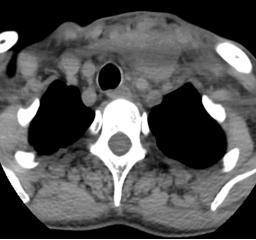

近日,60岁的张大姐,因咽喉痛、吞咽困难伴颈部肿痛一周在当地医疗机构抗炎治疗4天无效后随即来到桃源县中医医院耳鼻咽喉头颈外科就诊,经电子喉镜及颈部CT检查诊断为“急性会厌炎”,病情严重,接诊医生立即为其安排住院治疗。

(入院时颈部病情,入院时电子喉镜)

入院后,主管医生谢云波副主任医师积极予以完善相关检查,诊断为:“1、急性会厌炎,并脓肿形成;2、颈部脓肿;3、咽旁脓肿”。